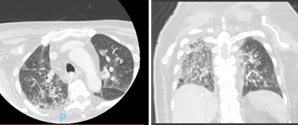

Por fim, teve episódio de dispneia e dessaturação associada, com tosse produtiva e um pico febril. No raio-x de tórax apresentava um padrão algodonoso no hemitórax direito, no entanto, tendo em conta o risco trombótico, realizou angiografia por TC (angioTC) torácica para exclusão de tromboembolismo pulmonar que descrevia “Sem evidência de tromboembolismo pulmonar. Prováveis alterações inflamatórias/infeciosas pulmonares, com concomitante agravamento da doença oncológica de base, traduzida pelo aparecimento de secundarização pulmonar. Proeminência ganglionar mediastínica (para-traqueal direita) igualmente mais evidente neste estudo” (Figs. 22 e 23).

Figs. 22 e 23 : AngioTC tórax (corte axial e coronal) - Evidência de progressão de doença, com metastização pulmonar.